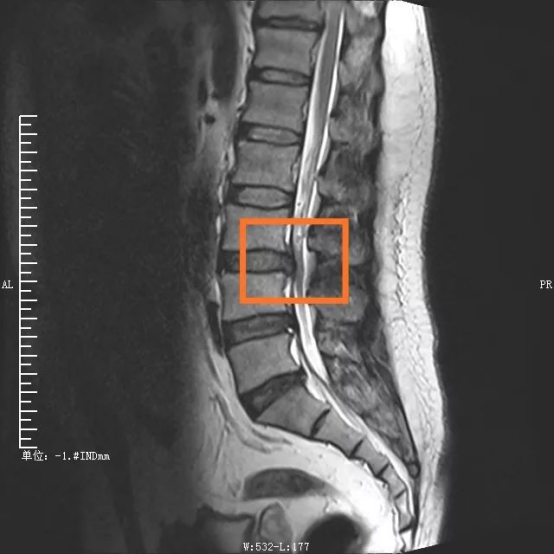

“如果说传统开放性腰椎手术走的是一条‘大刀阔斧’的路,那么OLIF则是走巧妙的创新之路。”主刀医生邓雷(重庆市医学会神经脊柱学组副组长)说道,患者陈先生被腰痛缠绕1年多,近段时间严重到走路都困难,经检查发现腰3/4椎间盘突出、腰椎管狭窄,属于典型的腰椎疾病。

手术部位术前/术后对比图

在外科医生眼中,衡量一台手术是否成功、是否属于微创范畴,术中的出血量、组织损伤、手术时间以及术后康复时间都是重要考量因素。传统腰椎手术从后方入路,需要切开分离肌肉组织,手术创伤大,时间长,出血量多。考虑到传统手术对患者肌肉等组织损伤较大,且手术费用及住院时间增加,脊柱脊髓专业组决定采取更安全高效的OLIF手术。